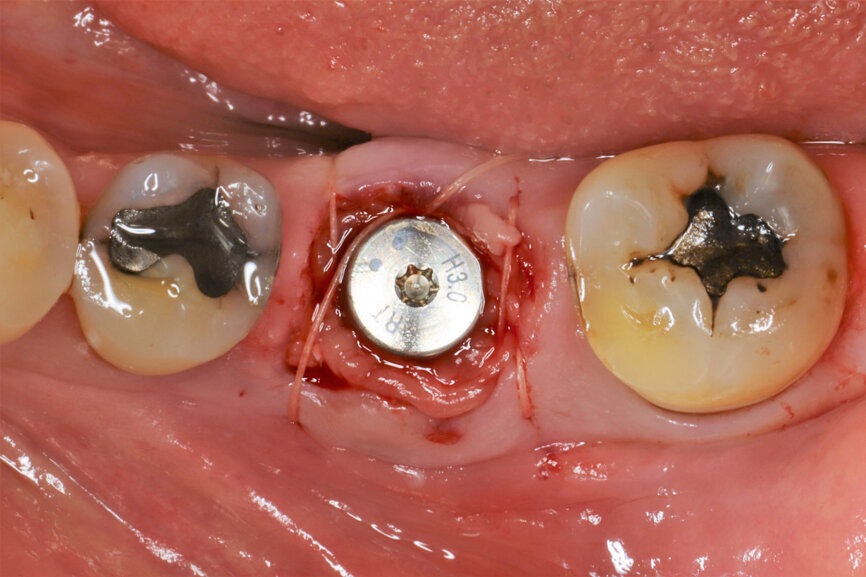

Fig. 16: Sutures to stabilise the biomaterials in place.

It was possible to verify solid interradicular bone availability (Fig. 5), extending further the limits of the root apices and allowing for a centrally oriented osteotomy. The implant bed preparation started with the use of a needle drill at 800 rpm, followed by the ⌀ 2.2 mm and ⌀ 2.8 mm drills (Figs. 6–10). The implant was placed with the use of ratchet and torque control, reaching the desired final position at a 50 N cm torque value (Figs. 11–13). The socket was then augmented with bovine-derived bone substitute impregnated with advanced platelet-rich fibrin (A-PRF) and finalised with sutures to keep the A-PRF application immobile, and a 3 mm healing abutment was placed (Figs. 14–17).